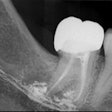

Save Your Tooth Month Q&A with Dr. Samuel Low